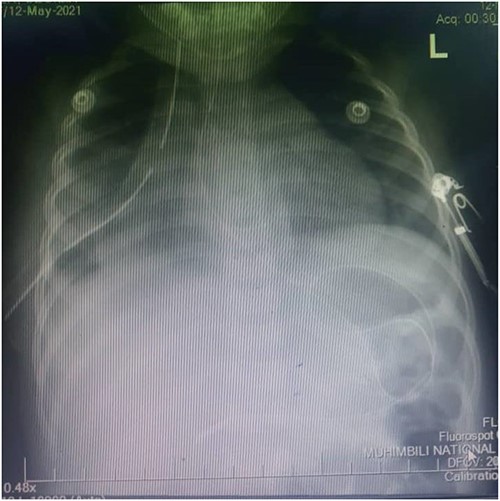

A one-year-old female child was admitted in Emergency Department after being involved in a motor traffic crash as a passenger where she sustained injury to the right leg and blunt head-thoracic-abdominal trauma. After resuscitation and supportive therapy, she underwent plain chest x-ray, which showed reduced right lung volume with elevated right hemidiaphragm and right upper zone opacity. The cardiac silhouette was obliterated in the right.

Figure 1 shows the plain chest radiography demonstrating the right lung atelectasis with elevated right hemidiaphragm and obliterated cardiac silhouette taken before laparotomy.